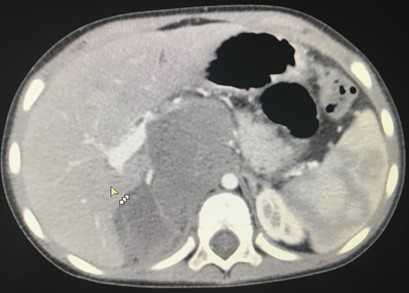

Эхография и РКТ позволяет значительно точнее определить анатомо-топографические и, в какой-то степени, морфологические характеристики нефробластомы (Рис. 1, 2). У всех наших пациентов опухоль была представлена объёмным образованием в виде солитарных масс преимущественно неправильной формы (95,2%). В области опухолевого узла контур почки был выпуклым (14,3%). В 50% обнаруживалась экзофитная зона с фрагментарно выраженной капсулой (71,4%). Эхографическая картина и изображение поражённой почки на РКТ были весьма схожи. Опухоль выглядела как негомогенная структура с преобладанием гиподенситивных очагов (90,5%). Эхографически кальцинаты при нефробластоме выглядят как редкие небольшие высокоинтенсивные сигналы и обнаруживались редко.

Рис. 1. Рентгеновская компьютерная томограмма опухоли почки. Чётко видно, как часть почки замещена опухолевой массой.

При в/в "контрастном усилении" (проведено у 33% больных) во всех случаях негомогенность усиливалась. Фокальные участки пониженной плотности ограничивались более резко выраженной линией демаркации, отделявшей опухоль от нормальной резидуальной почечной ткани. Капсула была выражена у 21,4% больных, что в совокупности с отсутствием метастазов позволило диагностировать I стадию заболевания всего в 4,8% случаев.

РКТ позволяет расшифровать ложноположительные и ложноотрицательные результаты, полученные при традиционной ретгенографии и эхографии, уточнить топику опухоли, её соотношение с сосудами, с высокой степенью достоверности выяснить наличие или отсутствие метастазов в лимфоузлах, кости и, по показаниям, в лёгкие.